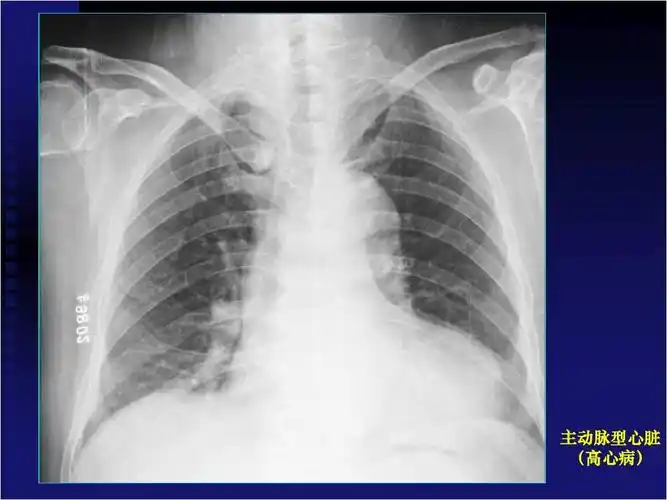

2)"主动脉"型:左心缘向外膨凸,心腰凹陷,主动脉结凸出,形如靴形.

梨形心靴形心烧瓶心这也样看平片想不会都难

梨形心:心脏形状像梨子一样,特点是肺动脉段凸出,左心室缩小,这提示